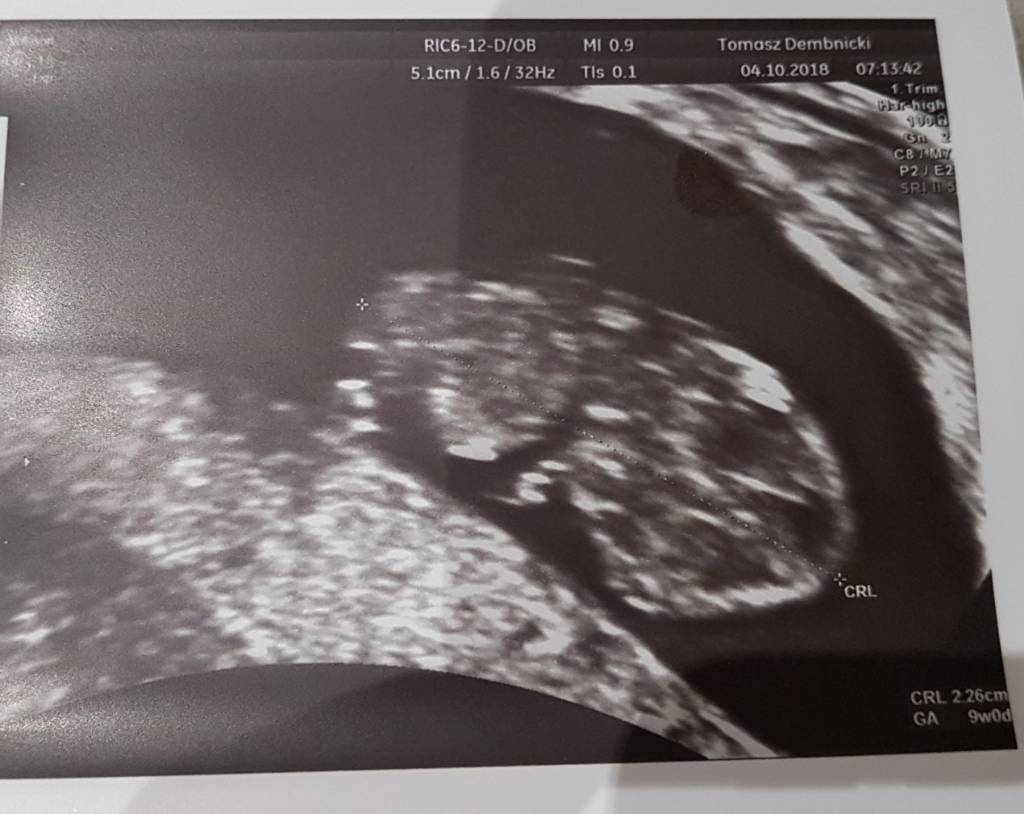

Witamy się w 9t0d, termin om jak na razie pokrywa się z usg. Grosik ma 2,2cm, serduszko uderza 160 razy na minutę [emoji4] Tp na 9.05.

20181004_190516.jpg

Załączniki

• 20181004_190516.jpg

73,3 KB · Wyświetleń: 678